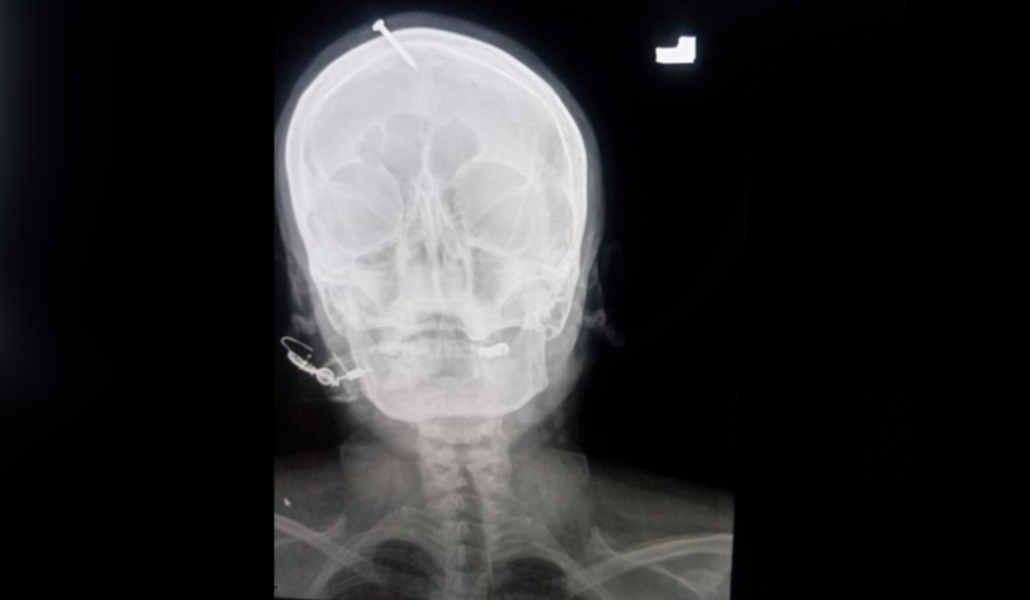

Պակիստանում երեք աղջիկ ունեցող հղին իր գլխին մեխ է խփել, որպեսզի տղա երեխա լույս աշխարհ բերի։ Նրան նման խորհուրդ տվել է տեղի հեքիմը։

«Մեխվելուց» հետո նրա ճիչը լսել են հարազատները: Վերջիններս փորձել են մեխը ինքնուրույն հանել տուժածի գլխից, բայց չեն կարողացել: Արդյունքում հղի կինը հոսպիտալացվել է՝ անգիտակից վիճակում և արնահոսելով: